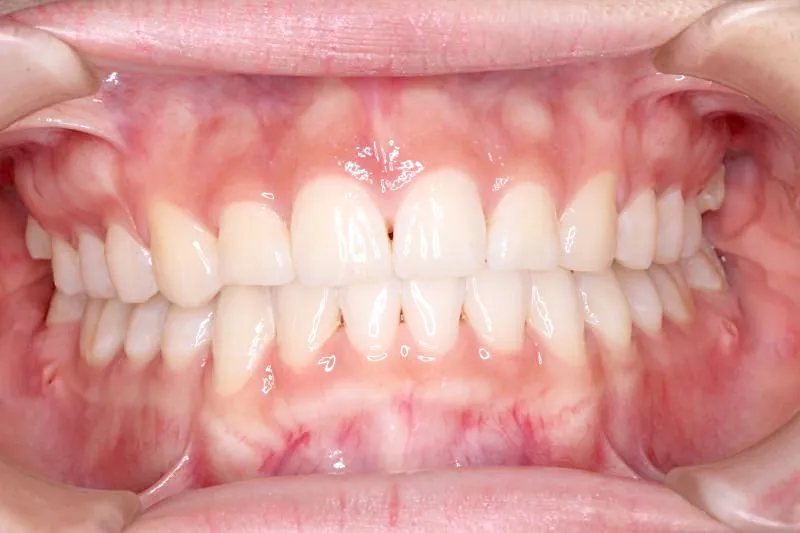

治療経過1

歯は抜かず、上下マルチブラケット装置を使用し治療いたしました。

治療回数54回、9年3ヶ月の治療期間で矯正治療を終了しました。

噛み合わせのずれは、ぱっと見綺麗に見えますが、放っておくとのちのち噛みにくくなり、顎関節にまで影響を及ぼしかねません。